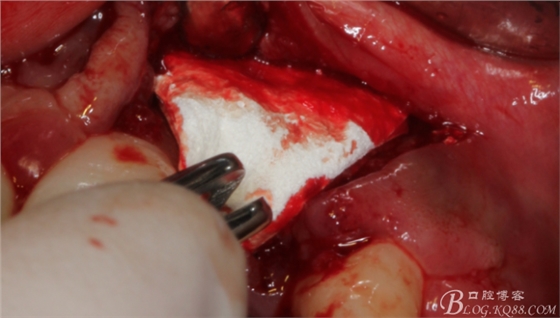

先行粘骨膜減張,取自體血液。

根方用取骨鉆取自體骨。

旋入一長(zhǎng)兩短3顆鈦釘。

將自體骨與BIO-OOS骨粉混合植到術(shù)區(qū),蓋生物膜。

縫合。